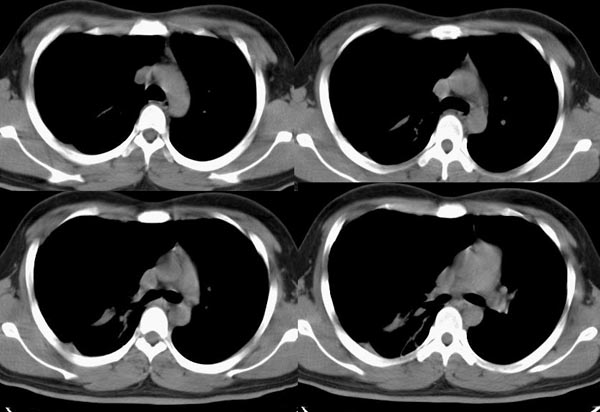

m21y既往体健,否认结核、支扩等病史;1周前患上感,无明显咳嗽,自觉无明显不适。单位体检透视时发现右侧液气胸!cr及ct如下(肺组织窗:l:-598hu w:1132hu):请大家会诊!!

右侧巨大含气囊性病变,壁薄、光整、其外侧见气体。右肺压迫性肺不张、胸腔内见少量积液。纵隔向左侧移位。左肺未见异常。诊断:1.右侧含气肺囊肿(先天性)。2.右侧液气胸。(少量液体)3.右肺压迫性肺不张。我也遇见一例这样的病人。女性。股骨外伤就诊。常规胸片发现右侧囊性病变。